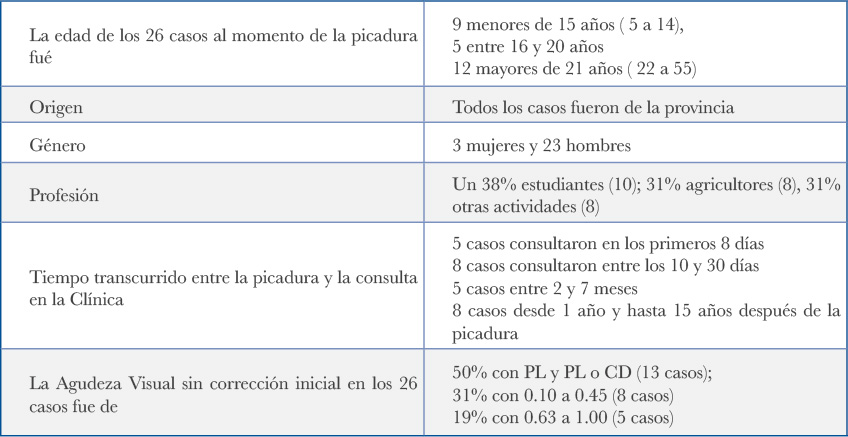

En el archivo fotográ co del Instituto Barraquer de América, encontramos 26 casos de pacientes con diagnóstico de Picadura de Avispa o de Abeja, que consultaron a la Clínica Barraquer de América en Bogotá en un período extenso de 50 años ( 1970 al 2020); se revisaron las Historias Clínicas, comprobando que correspondían a pacientes provenientes de diferentes regiones del país, con diferencias de edad, género, profesión, compromiso y evolución.

No fue posible la clasi cación entomológica del agente agresor, por no existir un Colombia un catálogo que combine el nombre popular en la región, con el nombre real en la clasi cación. Reportamos los nombres que relataron los pacientes, sin tener certeza absoluta sobre el agente agresor, como fueron: “ Boca pa bajo” ,“ Panelera” , “Cachicama”, “Vaquera” y “Lame Ojo” todos en referencia a Avispas; solo 9 casos como de “abeja Africana”, abeja “Chivata”, abeja “Abiojo”, abeja “Cintura amarilla”.

Presentamos aquí los 26 casos en una tabla ( Tabla No2). y a modo explicativo, un resumen de 9 casos con las fotos a su ingreso y resultado nal, para demostrar los diferentes grados de respuesta a la picadura, la magnitud del daño que puede ocurrir, y la evolución que tuvieron.

Síntesis de la Tabla No2

En los 26 casos la picadura fue en el Segmento Anterior: 25 en la córnea y 1 caso en el Limbo corneo-escleral.

Todos los casos habían recibido algún tipo de tratamiento y a la mayoría les habían retirado el aguijón antes de acudir a nuestro cuidado; solo 4 casos tenían el aguijón in Situ.

Entre los 25 casos corneales, en 13 la lesión comprometía todo el espesor, tenían descompensación corneal con severo edema, uveitis anterior tóxica y gran compromiso de la visión. Los otros 12 casos, tenían edema localizado alrededor de un leucoma de tamaño variable, o bien la córnea era trasparente con un leucoma puntiforme.

13/25 casos tenían opacidad de la cápsula anterior y/o catarata desde la primera consulta

21/25 casos CON despigmentacion del Iris, de los cuales en 13/21 SIN alteración de la función pupilar.

Los 8 casos restantes, 3 tenían discoria y pobre respuesta a la luz y 5 tenían Hipertensión y midriasis paralítica

4/25 casos SIN despigmentación del Iris y SIN alteración de la función pupilar.

El caso de picadura en el Limbo, (caso No17) tuvo leve despigmentación periférica inferior en el Iris, SIN compromiso de la función pupilar y la transparencia de la córnea en la periferia inferior quedo comprometida.

La agudeza visual de los 14 casos que pudieron ser tratados, fué alentadora durante el periodo que fueron controlados: ( casos del 13 al 26 en la Tabla No 2)

| AV sin corrección inicial: | AV con corrección nal |

| 7% : PL y PL (1 caso) | 7% : PL y PL (1 casos) |

| 38%: 0.10 a 0.40 ( 4 casos) | 14%: 0.10 a 0.40 (2 casos) |

| 28% : 0.67 a 1.00 (5 casos) | 72% : 0.67 a 1.00 (10 casos) |